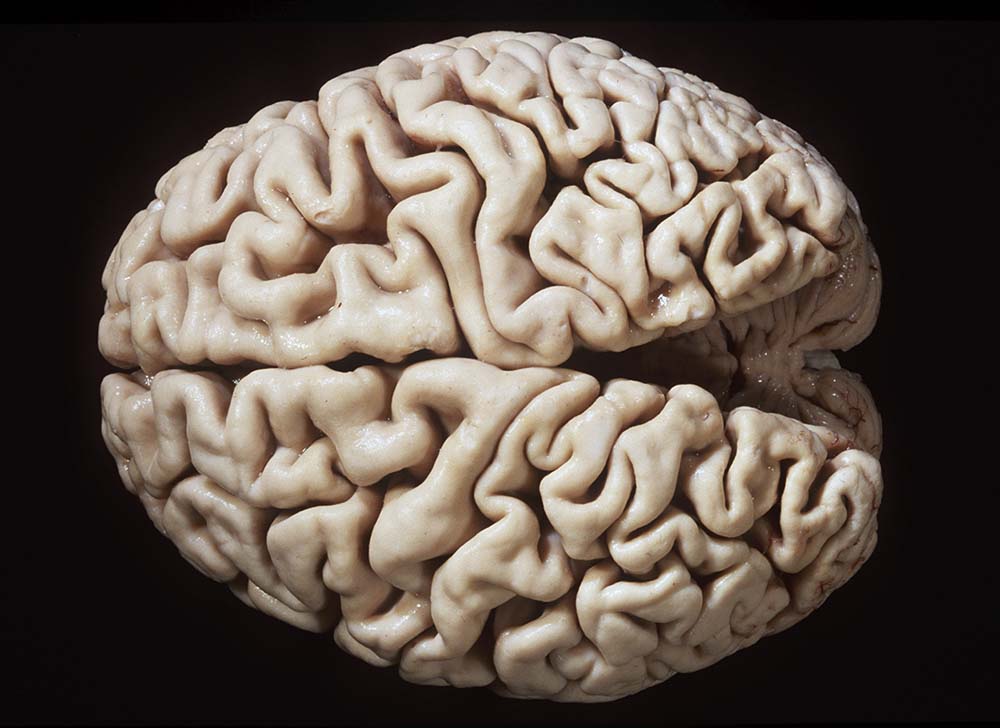

Gehirne von Alzheimer Patienten sind makroskopisch durch eine kortikale Atrophie (vor allem temporo-parietal) charakterisiert. Weiter findet sich meist eine deutliche Atrophie von Hippocampi und Mandelkernen. Diese geht einher mit einem Hydrocephalus internus (e vacuo), wobei vor allem die Temporalhörner der Seitenventrikel betroffen sind.

Makroskopie

Befund

Pathologischer Befund

Normalbefund